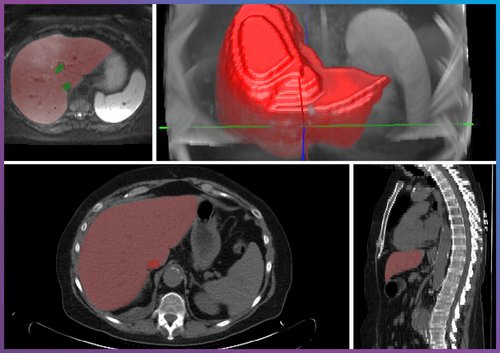

At Chimaera, we develop solutions that support the entire data-driven analysis process. Our offerings include precise annotations for AI training datasets, automated or semi-automated segmentations, and interactive 3D visualizations that allow clinical teams to intuitively explore complex structures. These tools provide a foundation for more reliable detection and quantification of pathological changes, including fat content determination, tumor segmentation, and volumetric analyses for surgical planning.

The combination of deep learning, structured data analysis, and interactive visualization allows researchers and clinical teams to use large image datasets more efficiently. This is essential for addressing issues related to liver disease, whether in clinical studies, translational research, or the development of image-based diagnostic tools.